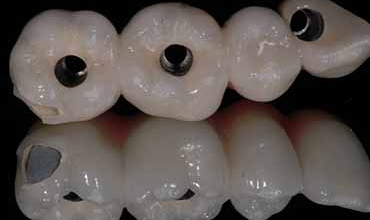

Prof Hom Lay Wang - Predictably Successful Periodontal, Oral Plastic And Implant Surgical Course

Prof Hom Lay Wang is ranked as the #1 in the world on the subject of peri-implantitis based upon “Expertscape” website. Prof. Hom Lay Wang , DDS, MSD, PhD, Professor and Director of Graduate Periodontics at the University of Michigan. Prof Wang published one textbook, more than 30 book chapters/invited reviews and more than 500 scientific articles.